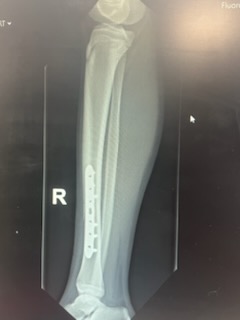

I’m happy to say that the surgery went well. He had a metal plate attached to his tibia with screws, and a new cast below the knee.

The metal plate that has been screwed in to his tibia can be seen here. Weirdly it is quite close to the skin so you can see and feel it on his leg from the outside.

After 9-12 months he will have another operation to remove the metal plate. Then hopefully he will make a total recovery. We are all looking forward to that time.